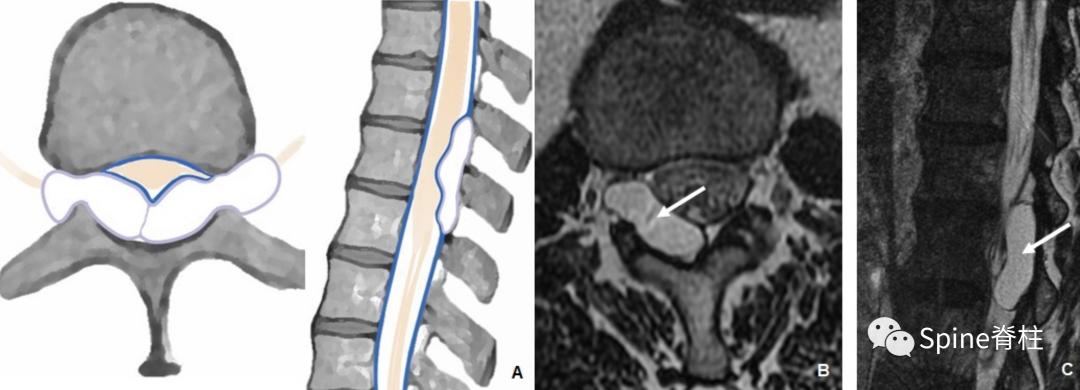

历史上称为神经根旁囊肿或 Tarlov 囊肿,这些囊性病变在硬膜和周围神经鞘之间的过渡处与蛛网膜下腔相通。它们可能包含感觉神经根,但多数无症状,累及腰骶部可累及数个神经根 (下图)。

一名73岁左臀部疼痛5个月患者。模式图提示根袖憩室(神经根旁囊肿)的典型外观(A)。黑箭头为通过硬膜缺损的蛛网膜突出。横断面和矢状面T2加权像提示左侧S1神经根袖囊肿,注意神经根的位置,粘附在囊壁(白色箭头,图B和C)

2. 硬膜内外层之间的囊肿 (II 型)

通常认为是解剖性硬膜膨出,腹侧硬膜外囊肿和椎管内蛛网膜囊肿。硬膜内外层之间的囊肿是由于内层硬膜的局部缺损导致内外层硬膜之间的撕裂 。脑脊液可能长时间在硬膜两层之间的积聚而导致囊肿形成。硬膜内外层之间的囊肿主要影响硬膜的腹侧部分,导致脊髓从前方受压(下图)。在有颈椎创伤病史的患者中,硬膜内外层之间的囊肿通常影响靠近颈神经根袖的硬膜外侧部分。诊断的主要的挑战是硬膜缺损的定位,这通常需要 CT 或 MR 脊髓造影。

一名58岁患者,有 5 个月车祸后进行性脊髓病病史。 模式图提示硬膜内外层之间的囊肿的典型外观(A) 。矢状位 (B) 和横断面 (C) 颈椎MPR FIESTA MR图像提示从C4-T1硬膜撕裂,但不伴有脊髓疝

当这些硬膜内外层之间的囊肿与脊髓疝相关时,应考虑先天性或退行性改变。脊髓疝可导致进行性脊髓病,引起脊髓半切综合征Brown-Sequard综合征。在这种情况下,硬膜缺损可以通过MRI很容易定位,因为疝的位置标志着缺损部位(下图)。

一名50岁硬膜撕裂伴脊髓疝患者。模式图和横断位T2加权像提示T4水平脊髓前移(A)。FIESTA图像(B)提示脊髓伴右侧腹外侧硬膜突出(箭头)